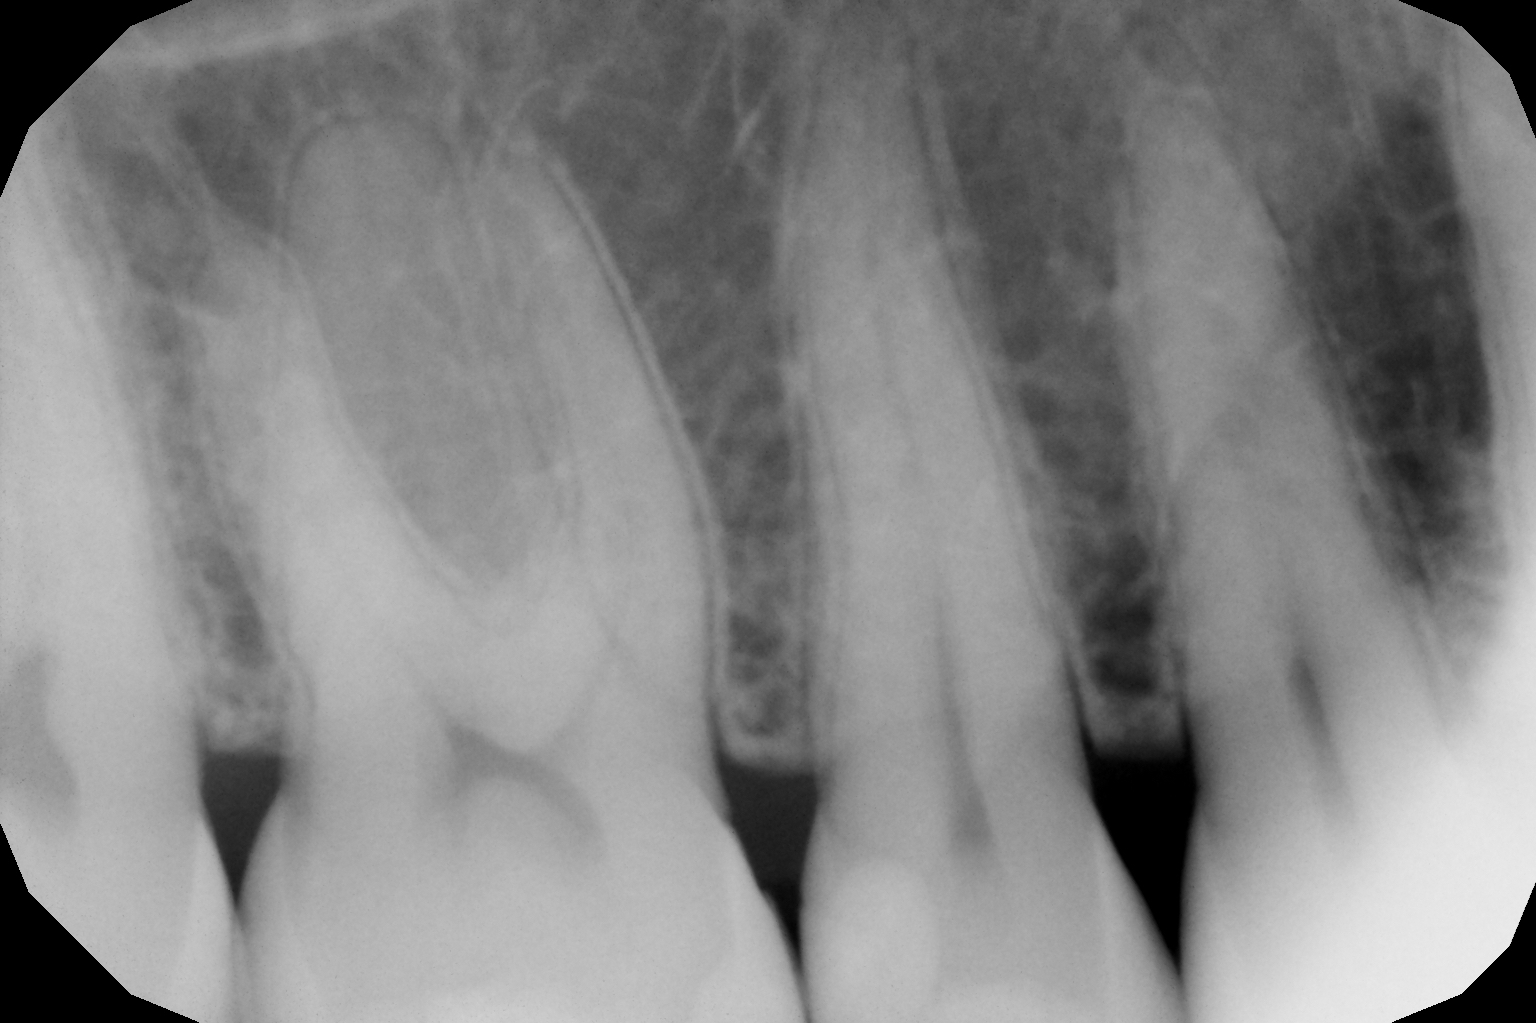

Si presenta alla nostra attenzione per dolore in zona premolare e molare del primo quadrante. Dopo un’analisi clinica e strumentale con radiografie e test diagnostici, si evidenzia la necessità di sostituire le precedenti otturazioni in composito, al fine di consegnare un migliore punto di contatto (fenomeno dell’impact food).

foto 12 Aspetto radiografico